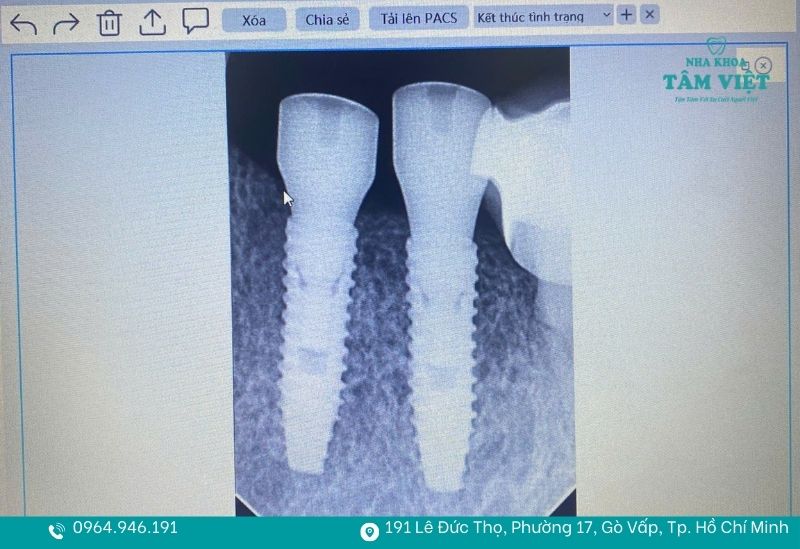

Răng implant có cấu tạo gồm trụ Titanium được cấy trực tiếp và tích hợp vững chắc vào xương hàm. Nhờ cơ chế này, implant đóng vai trò như một chân răng thực thụ, giúp phục hồi khả năng ăn nhai lên đến hơn 90%. Người sử dụng có thể thoải mái thưởng thức các món ăn yêu thích, kể cả những loại thức ăn dai, cứng hay giòn mà không cần kiêng khem khổ sở.